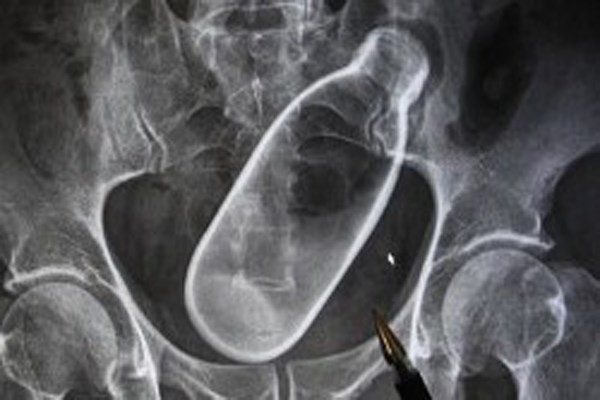

| Các bức hình chụp X-quang cho thấy cả một chai nước nằm hoàn toàn trong hậu môn của bệnh nhân này. Ông cho biết, trước đó đã mắc chứng táo bón trong một thời gian dài nhưng không làm sao chữa khỏi. Vì vậy, ông quyết định làm liều bằng cách lấy chai nước đưa vào hậu môn để “kích thích”. |